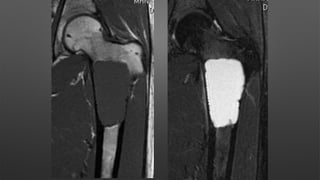

Giant Cell Tumor

• A benign aggressive tumor typically found in the metaphysis of long bones

• Age & sex

• more common in females

• ages 30-50 years

• Location

• distal femur > proximal tibia > distal radius > sacral ala

• distal radius is third most common location

• phalanges of the hand is also a very common location

• Operative

• Extensive curettage and reconstruction (with adjuvant treatment)

• In lesions amenable to curettage

• if no cortical breakthrough treat with curettage and cementing

• if significant cortical breakthrough consider intercalary resection (with free fibular graft)

vs. amputation

• challenge of treatment is to remove lesion while preserving joint and providing support to

subchondral joint

• extensive exterioration (removal of a large cortical window over the lesion) is required

• can fill lesion with bone cement or autograft/allograft bone

• 10-30% recurrence with curettage alone verses 3% with adjuvant treatment